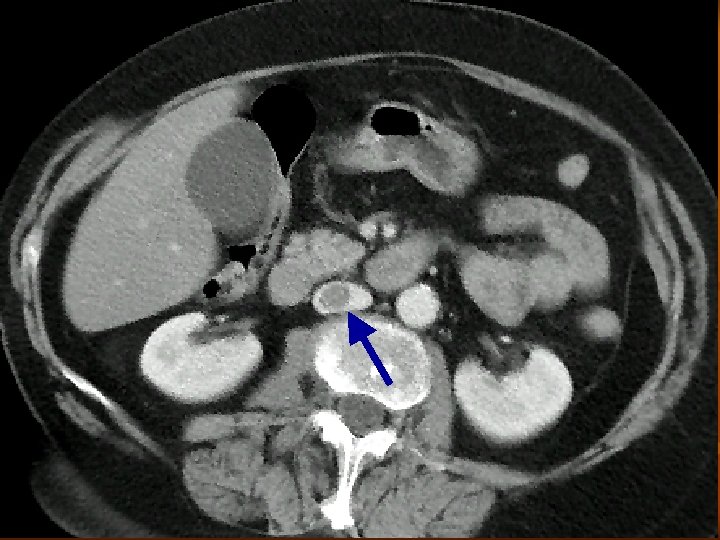

A CTA leggyakoribb alkalmazása n Mellkasi és hasi aorta, valamint iliaca rendszer vizsgálata aneurysma esetén a CTA pontos választ ad: - nagyság – növekedés - kiterjedés – kiinduló erek érintettsége - trombotizáltság - ruptura fennállása – haematoma

A CTA leggyakoribb alkalmazása dissectio esetén a CTA pontos választ ad: - dissectio fennáll vagy nem a dissectio kiterjedése, típusa kettős lumen megléte pericardium érintettsége supraaorticus ágak érintettsége visceralis ágak érintettsége ruptura occlusio esetén a CTA pontos választ ad az elzáródás helyére, collateralis keringés kialakulására, a parenchyma károsodására

A CTA leggyakoribb alkalmazása n n n Renovascularis és cerebralis vasculatura obliterativ folyamatának meghatározása Abdominalis és thoracalis daganatok műtéti eltávolítása előtt vasculatura ábrázolása Pulmonalis embolia gyanújának esetén! Első vizsgálati lépésként!